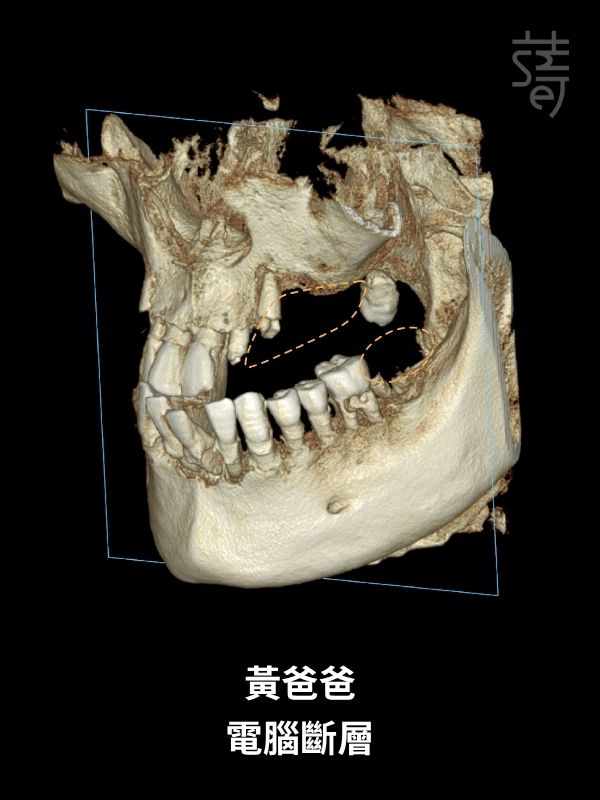

不同於一般診所僅拍攝局部影像,蒔美採用高階全頭顱 CT 掃描,

完整呈現從頭頂到下巴的顏面立體結構,確保醫師能精準避開所有風險區域。

此技術專為嚴重缺骨患者設計,特別適合上顎骨幾乎全數流失、傳統方式已無法重建的情況。

顴骨位於眼眶下方外側,骨質緻密且穩定,不易隨時間吸收。

即便上顎骨基底幾乎完全流失,將植體直接固定於強壯的顴骨,仍能建立牢固的支撐。

不過,顴骨植牙屬於技術門檻極高的手術,植體需穿越萎縮的上顎骨,固定在堅硬的顴骨。

長達 30~52mm 的植體比傳統更長,雖然支撐力更強,但對醫師操作的精準度要求極高。